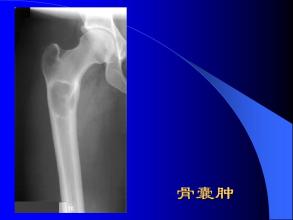

骨囊腫

骨囊腫是骨的瘤樣病變,又名孤立性骨囊腫。囊壁為一層纖維包膜,囊內為黃色或褐色液體。主要以手術治療為主,預后良好。